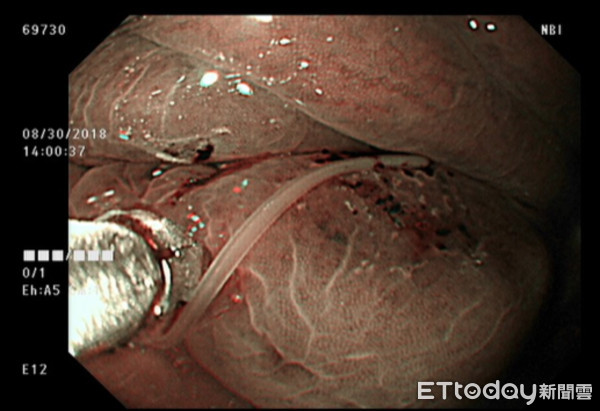

▲她吃完海鮮野味腹劇痛,胃鏡驚見「活蟲死咬胃壁不鬆口」。(圖/臺安醫院提供)

這種僅局限在胃體部的發炎並不常見,顯然得更小心。此時胃皺褶是強烈收縮的,將胃吹氣擴張後,果然在皺摺發炎處找到兇手: 一隻白色近透明的小蟲。

我用切片鉗開始抓蟲,蟲體很小並不好抓,瞄準後沒想到這隻活蟲死死咬住胃壁不肯鬆口(可以想見患者有多痛!),需要再拉幾下才離開胃壁,蟲體立刻蜷曲在切片鉗上。接著就簡單了,蟲體取出後、泡至福馬林檢體盒,它掙扎約幾分鐘後就靜止不動了,送驗證實是海獸胃線蟲。